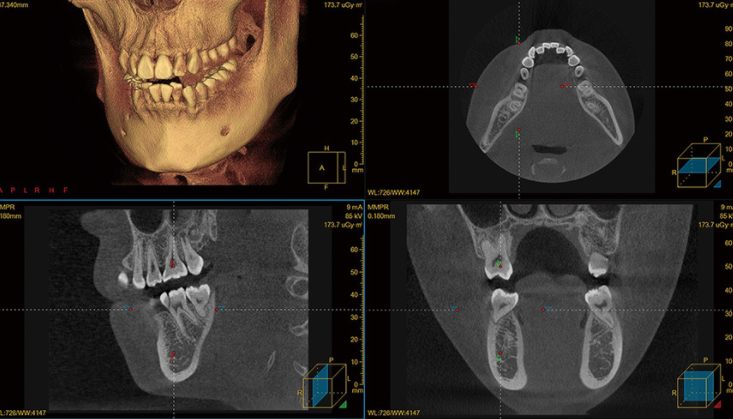

CT片

再者,就要說說這個(ge) CBCT片,簡稱CT片。通常是拍曲麵斷層發現問題不能準確判斷的時候需要做的檢查,畢竟CBCT片是三維的,可以從(cong) 片子上了解到二維的曲麵斷層片看不到的牙齒情況。比如,正畸牽引以及正頜手術通常都需要拍牙齒ct片。

CT片和全景片有什麽(me) 區別

相比全景片來說,借助ct片,醫生通常可以更為(wei) 立體(ti) 、清晰和直觀的看到牙齒的情況,尤其是有埋伏牙的情況,所以雖然口腔ct器械並不便宜,但由於(yu) 它對於(yu) 牙科有重要重要,不少專(zhuan) 業(ye) 口腔機構和大醫院都引進了ct機,並把cbct檢查也列為(wei) 了正畸常見的檢查項目。